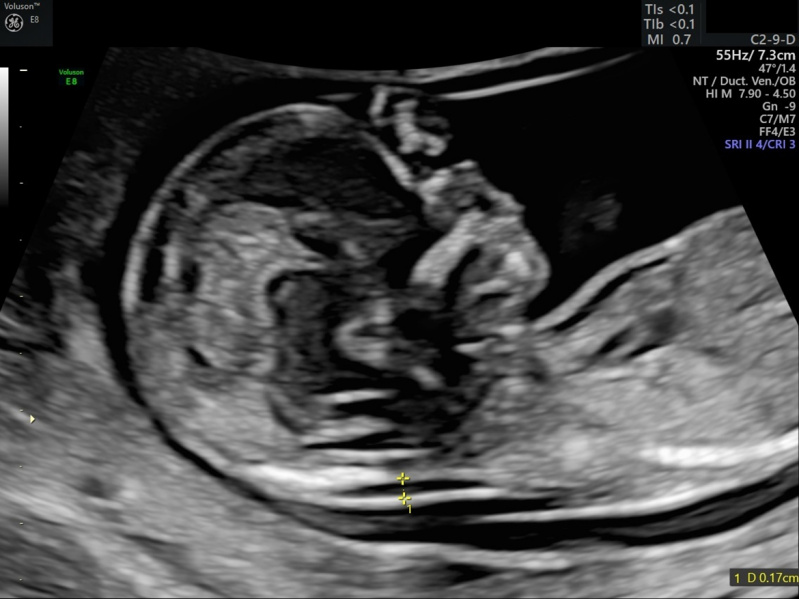

Sinds de invoering van prenatale screening in Nederland in 2007 en het aanbieden van echozorg in de eigen praktijk, hebben verloskundigen, echoscopisten en artsen behoefte aan geaccrediteerde nascholing in hun eigen praktijk, echocentrum of ziekenhuis. Scholing gericht om meer kennis te vergaren maar ook hands-on om de beeldvorming te verbeteren en orgaanstructuren beter te herkennen.

Na het volgen van een opleiding echoscopie werden werkafspraken aangepast, protocollen kregen een update en het echo-apparaat werd vervangen door een nieuwer model. Een opfriscursus op z’n tijd zou dan best wel fijn zijn. Vooral ook om het echo-apparaat ten volste te benutten. Ik bied hands-on scholing op maat aan op de eigen praktijk of ziekenhuis. Op deze manier wordt gewerkt met het echo-apparaat wat het meest vertrouwd is voor de cursist.